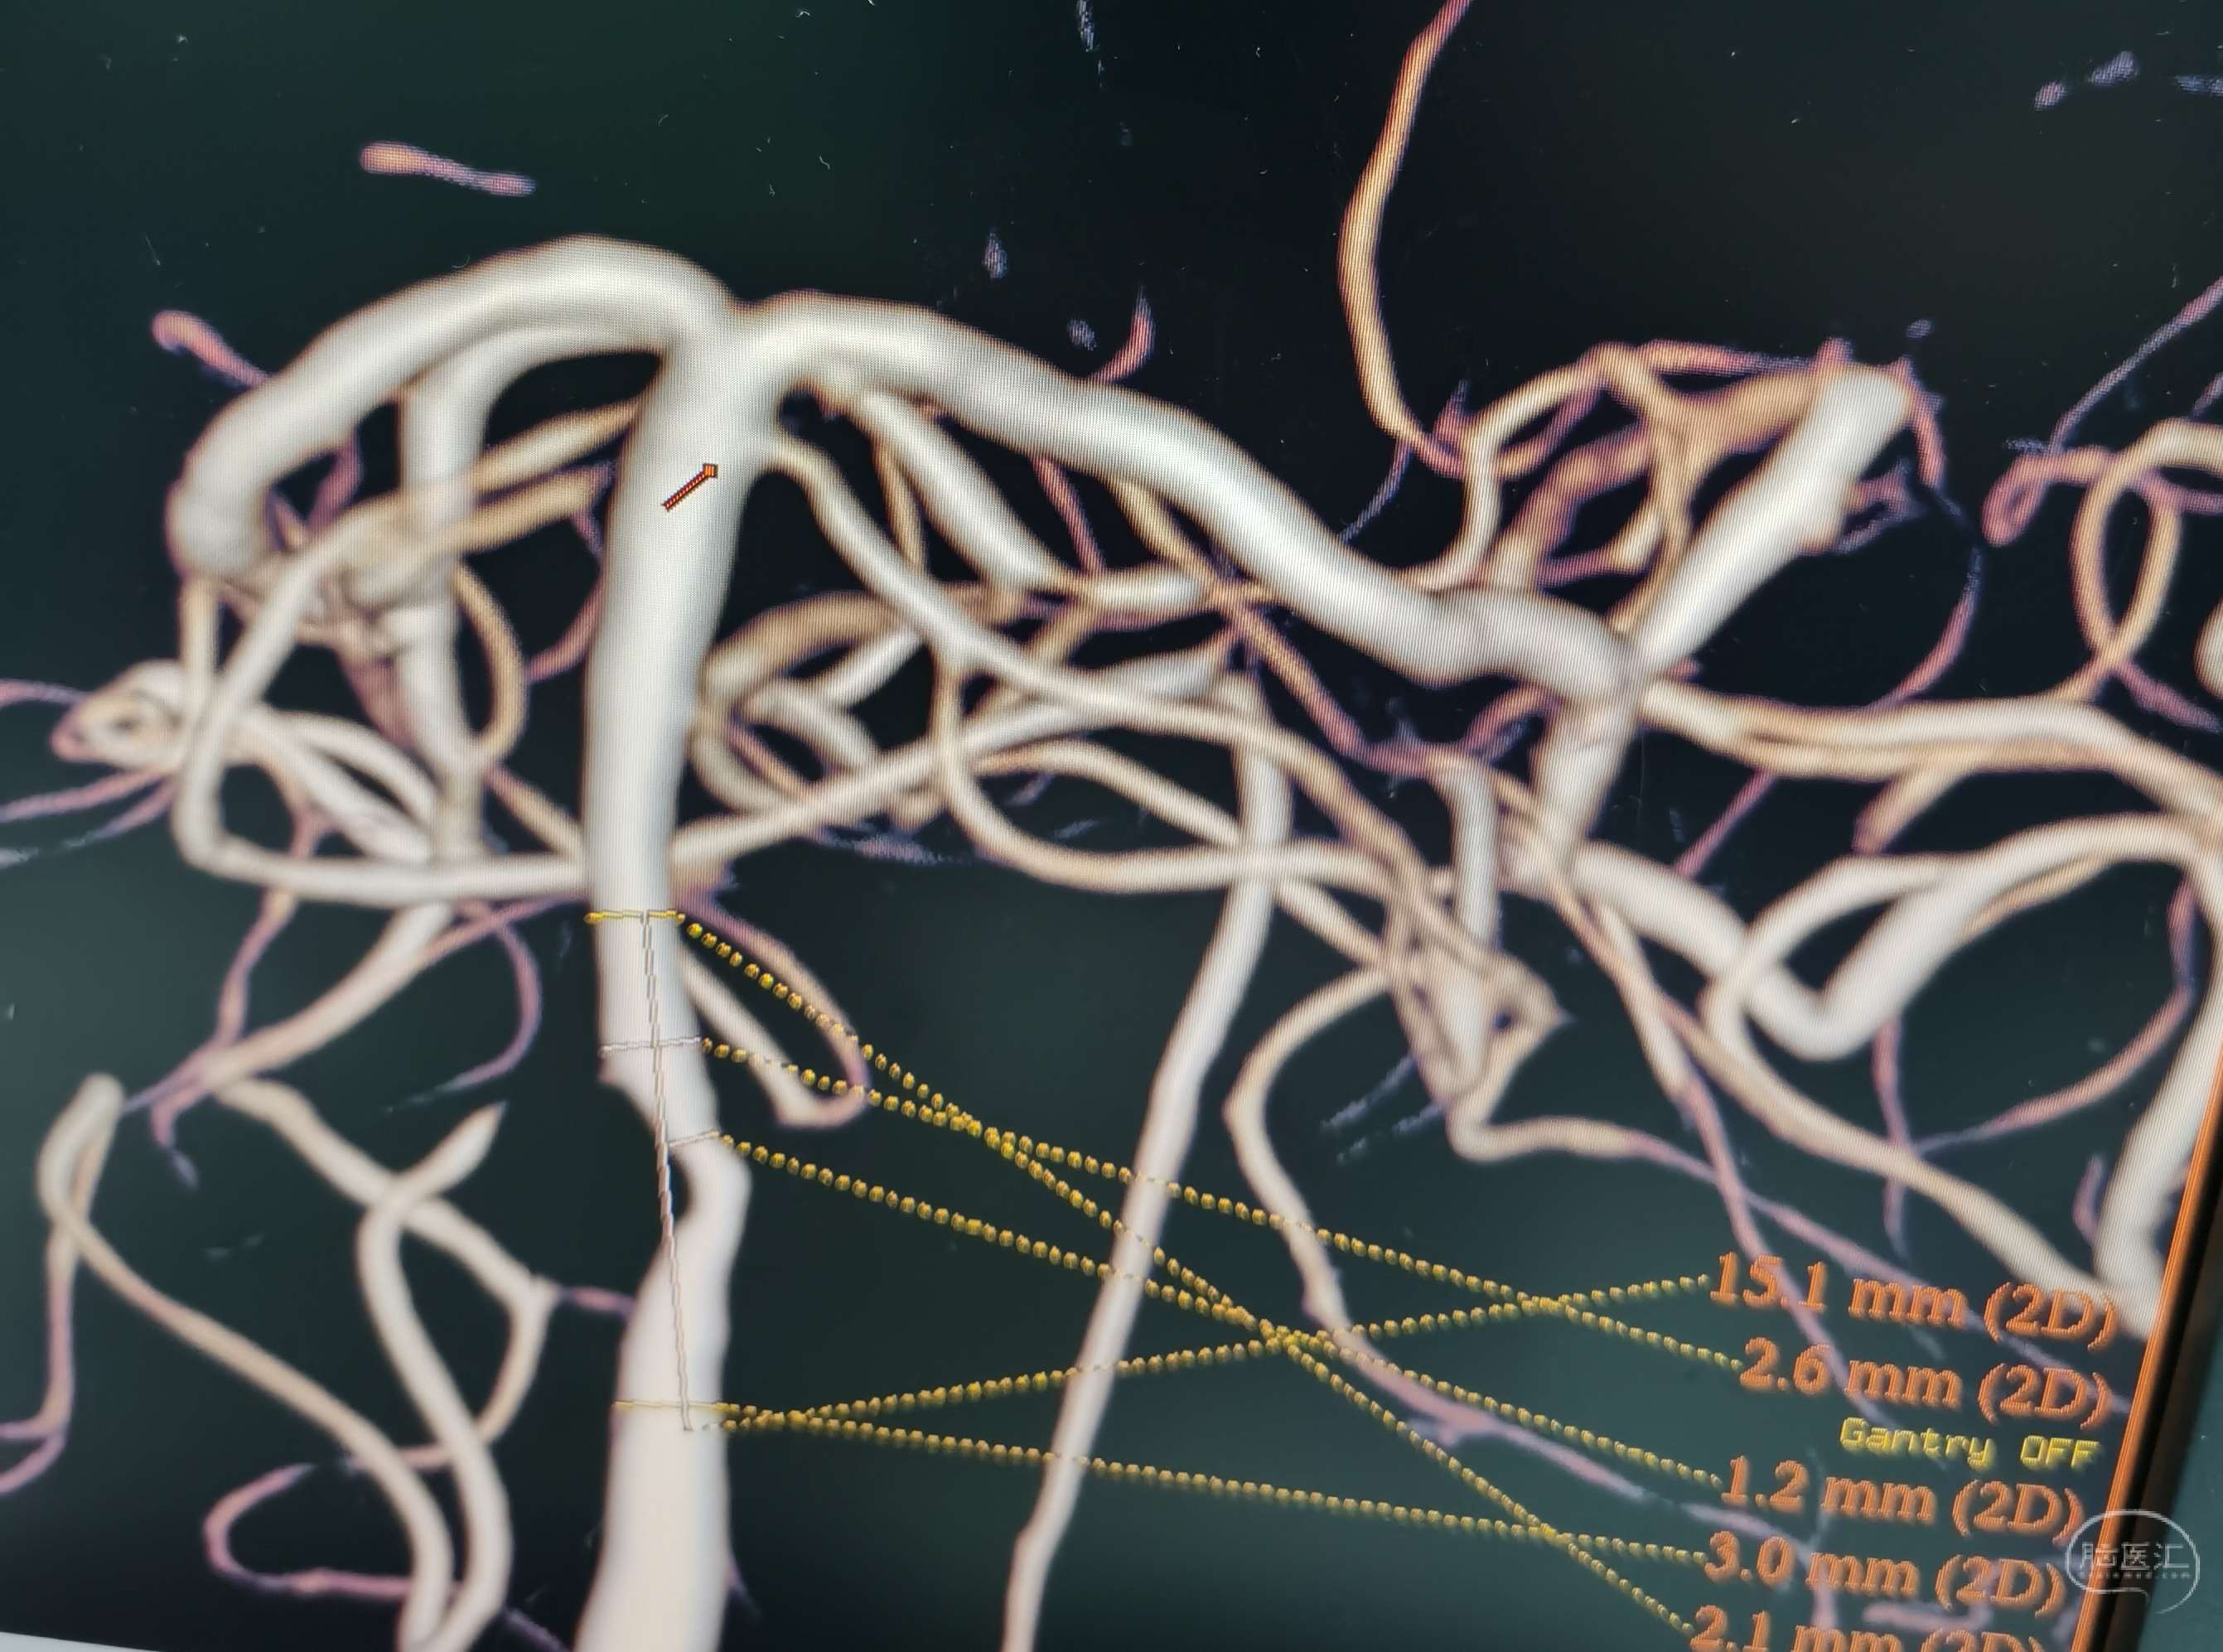

DSA示:基底动脉中下段重度狭窄。

3D重建。

先用Gateway2.5×13mm预扩。

置入NeuformEZ 3.5×20mm支架。

血管狭窄明显改善。